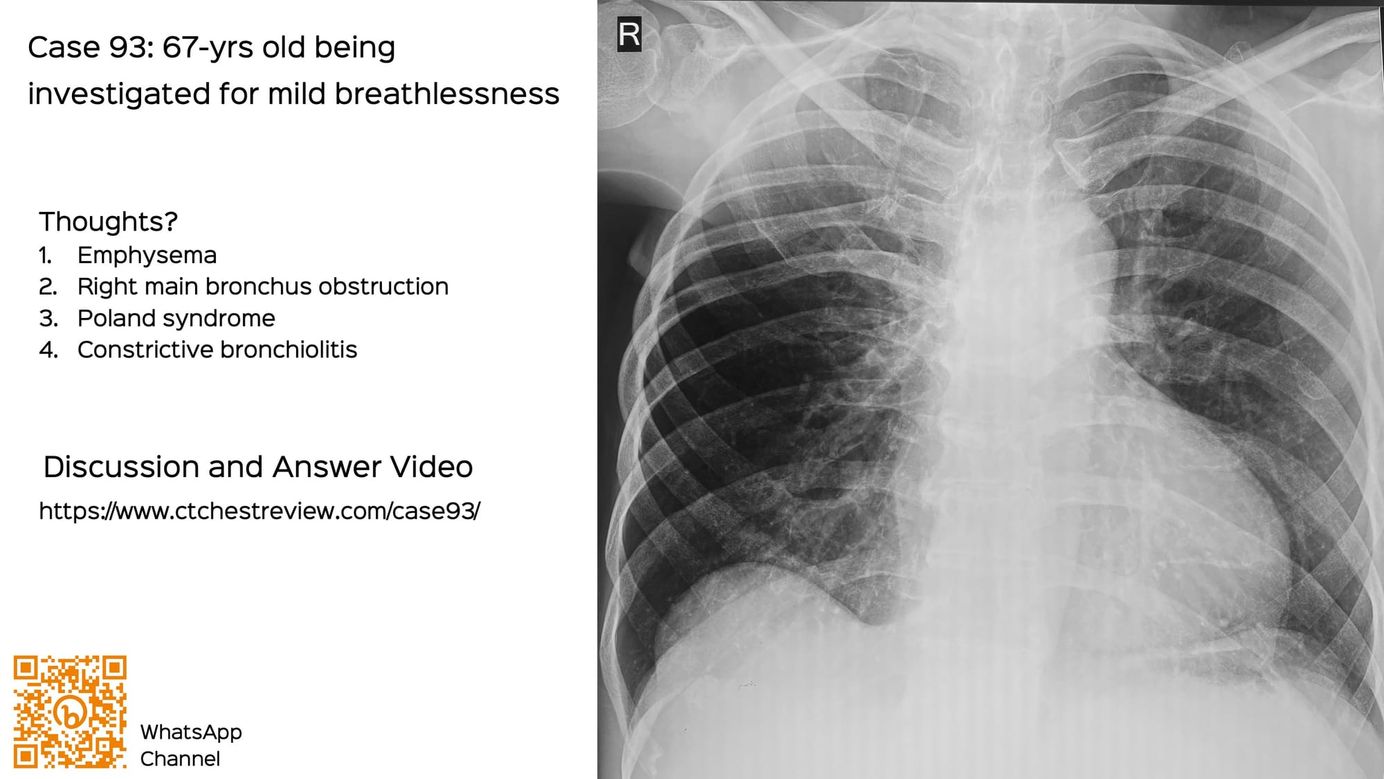

A 67-years old patient presented without any prior diagnosis to a pulmonologist for mild breathlessness. The chest radiograph was unusual.

Thoughts?

- Emphysema

- Right main bronchus obstruction

- Poland syndrome

- Constrictive bronchiolitis